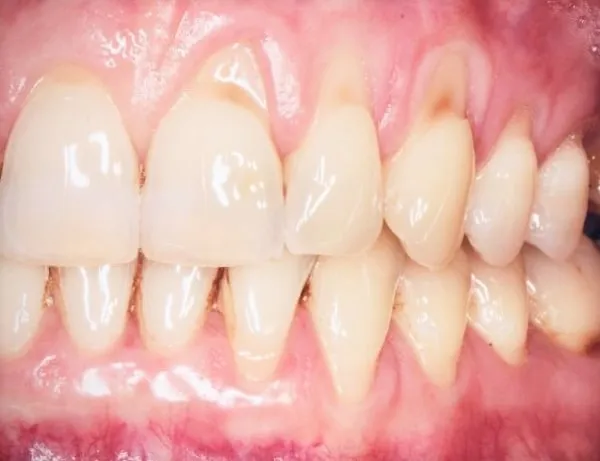

Recesja dziąseł to stan, w którym linia dziąseł stopniowo się cofa, odsłaniając szyjki, a czasem nawet korzenie zębów. Dla wielu pacjentów jest to powód do niepokoju, ponieważ odsłonięte części zębów są bardziej wrażliwe na bodźce zewnętrzne, takie jak zimno, ciepło czy słodkie pokarmy. Co więcej, odsłonięte korzenie są znacznie bardziej podatne na rozwój próchnicy, a sam proces recesji może prowadzić do wydłużenia zębów, co negatywnie wpływa na estetykę uśmiechu. Problem ten jest dość powszechny; szacuje się, że dotyka znaczną część dorosłej populacji w Polsce, a jego występowanie często wzrasta wraz z wiekiem. Świadomość pacjentów na temat zdrowia jamy ustnej rośnie, co sprawia, że coraz więcej osób szuka rozwiązań dla problemu cofających się dziąseł.

- Recesja prowadzi do odsłonięcia szyjek zębowych, powodując nadwrażliwość, zwiększone ryzyko próchnicy korzenia i problemy estetyczne.

Przeszczep dziąsła jest jedną z najczęściej stosowanych i najskuteczniejszych metod chirurgicznej odbudowy tkanki dziąsłowej. Procedura polega na pobraniu niewielkiego fragmentu tkanki łącznej, zazwyczaj z podniebienia pacjenta, i przeszczepieniu go w miejsce recesji. Zabieg ten pozwala na pokrycie odsłoniętych szyjek i korzeni zębowych, co redukuje nadwrażliwość, chroni przed próchnicą korzenia i znacząco poprawia estetykę uśmiechu. Jest to szczególnie polecane w przypadkach znacznego odsłonięcia korzeni lub gdy recesja jest bardzo widoczna.